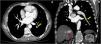

Un hombre de 49 años presentó sangrado de várices esofágicas y, además, se le diagnosticó cirrosis relacionada con enfermedad de hígado graso asociado a disfunción metabólica. El paciente fue referido a continuación a nuestro centro para investigar nódulos hepáticos detectados por medio de ultrasonido. El paciente estaba asintomático, con una clasificación de Child-Pugh A5 y puntuación de MELD de 12. Una tomografía computarizada (TC) de contraste del abdomen mostró CHC multinodular/infiltrante, con un trombo tumoral en la vena hepática derecha que se extendía a la vena cava inferior (fig. 1). Además, se identificaron émbolos en el lóbulo inferior del pulmón izquierdo en la TC de tórax (fig. 2). La alfafetoproteína sérica fue de 509 ng/ml, el gammagrama óseo no presentó alteraciones y el ecocardiograma transtorácico no mostró extensión al corazón.

Tomografía computarizada en la fase arterial. Las flechas amarillas muestran defectos de llenado parciales en las ramificaciones arteriales de segmento en el lóbulo inferior del pulmón izquierdo, que corresponde a embolia pulmonar. No existe evidencia de metástasis pulmonar. La flecha roja revela trombos tumorales dentro de la vena hepática derecha. A) Plano transversal. B) Plano coronal.